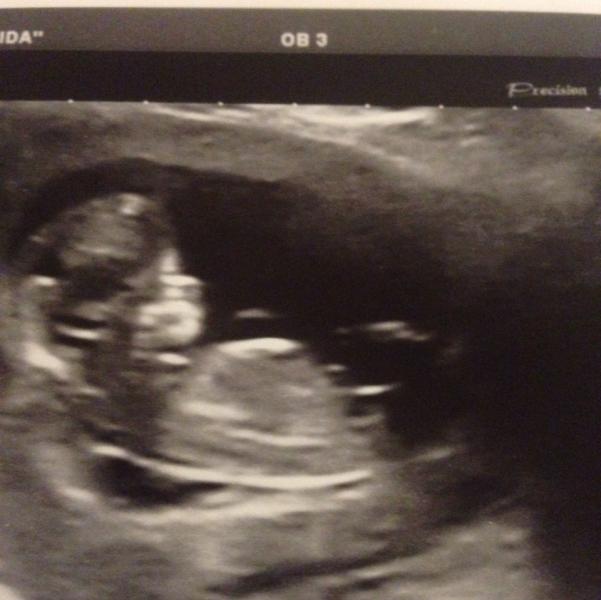

Пережила я сегодняшний скриннинг!! УЗИ в исиде делала Петренко! Сначала я ее даже испугалась. Она так спрашивала меня о сроке как будто учительница перед доской !!! Потом долго смотрела , че то диктовала и все время говорила о гипертонусе!!!! Я даже дышать боялась!! Но в целом сказала что по УЗИ с манюней все хорошо!!!;)) остальное будет ясно когда будут результаты квадротеста!! Часть завтра, часть через неделю !!! Я перепуганная почапала к своему доктору - че делать то с тонусом !!!! И тут сюр...